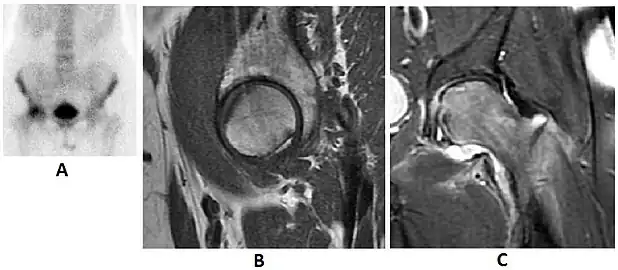

Radiological signs of transient osteoporosis of the hip include localized osteoporosis of the femoral head and neck (Figure 8). Nevertheless, final diagnosis has to be made with MRI to differentiate it from avascular necrosis and from insufficiency or stress fractures of the femoral head or neck. In case of AVN, radiographs can only demonstrate delayed or advanced signs. Staging according to Ficat classification ranges between normal appearance (stage I), slight increased density in the femoral head (stage II), subchondral collapse of the femoral head with or without “crescent” sign (stage III), and advanced collapse with secondary osteoarthritis (stage IV). In the case of stress or insufficiency fractures X-ray sensitivity has been proven to be much lower than MRI, which is currently the gold standard.[1]

Figure 8:

X-ray of a patient with transient osteoporosis of the left hip showing osteoporosis.[1] -

Coronal stir imaging in transient osteoporosis, showing diffuse edema.[1] -

Scintigraphy (A), sagittal T1 (B), and coronal PD fat sat of a patient with a subchondral fracture of the femoral head with convex shape to the articular surface.[1] -

Coronal T1 of a patient with avascular necrosis of the femoral head.[1]